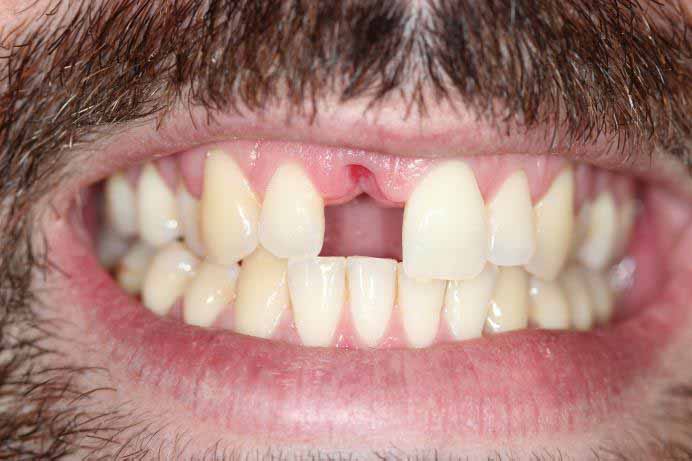

Broken Upper Front Tooth

The upper right central incisor tooth broke and was irreparable. Following removal of this tooth, and implant was placed on the same day as well as a temporary crown. This gave the patient a replacement tooth immediately and after 3 months of healing, a more definitive crown was made to match closely the adjacent tooth.